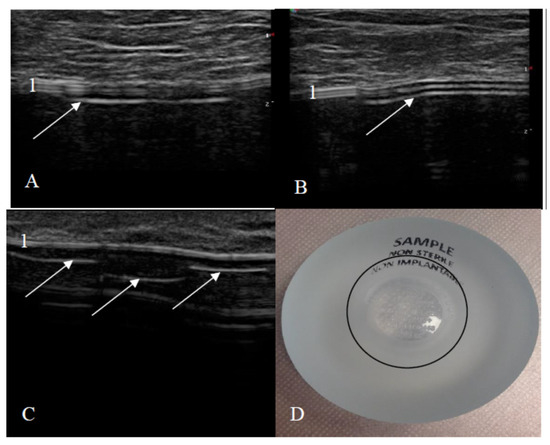

US examination signs of an intact and a ruptured breast implant were chosen with reference to literature and examined breast implants were divided into two groups—intact and ruptured [23,24]. An intact breast implant was characterized by an even and continuous implant shell and homogeneous intracapsular echotexture (Figure 1).

Figure 1. Signs of an intact implant on ultrasound: (A) a textured-surface implant (manufacturer Mentor) and (B) a smooth-surface implant (manufacturer Motiva); 1—shell (two parallel white lines); 2—homogeneous content; 3—implant shell wrinkle with small amount of peri-implant fluid; 4—shell (three parallel white lines).